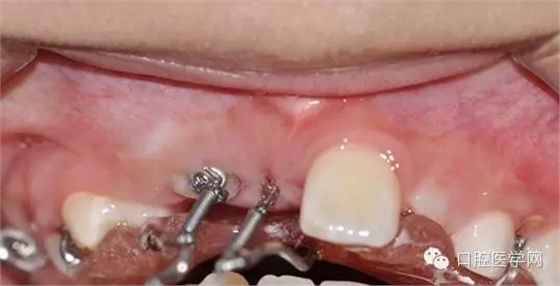

一周后拆線 :

術(shù)前已經(jīng)給小孩取了牙模,所以就開始

“活動(dòng)可調(diào)、釣魚式牽引器”的制作。(后續(xù)的博客會(huì)詳細(xì)的給大家講一下制作要領(lǐng),和各種卡環(huán)變異的彎制。簡(jiǎn)簡(jiǎn)單單的彎制卡環(huán)可以完勝各種焊接或鑄造。 )

帶入口內(nèi)調(diào)整吊桿方向加輕力: